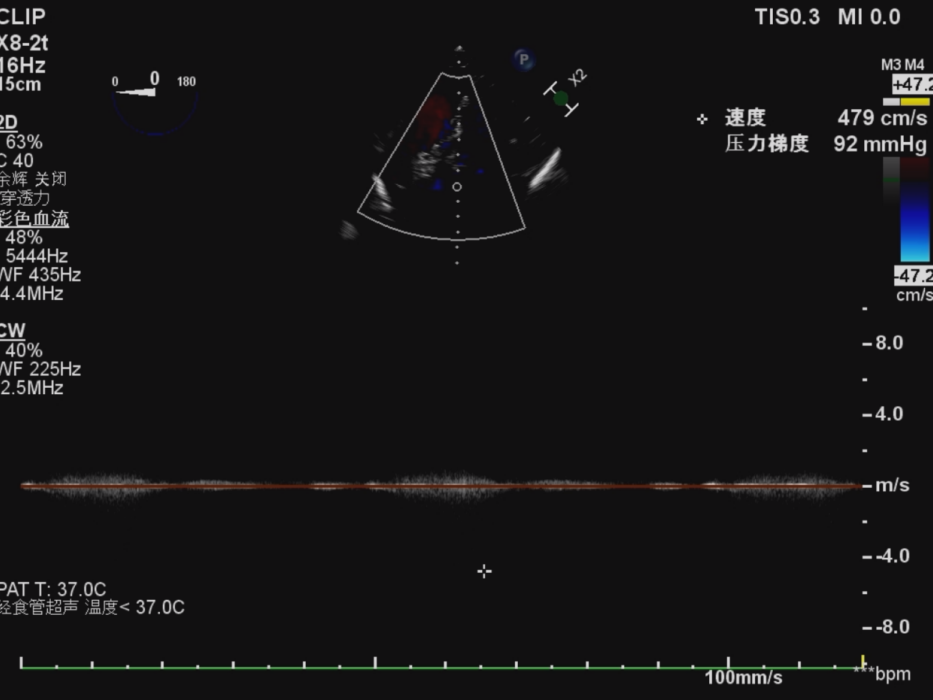

心脏超声提示左室壁不均匀增厚、左室流出道收缩末轻度梗阻、主动脉瓣钙化,瓣口重度狭窄并轻微反流。左室流出道面积2.0cm²,收缩末左室流出道压差24mmHg,主动脉瓣增厚、钙化,呈团块样,分界不清,开放面积0.4cm²,流速532cm/s,峰值压差113mmHg,平均压差70mmHg。主动脉瓣口见反流束局限于瓣口。

术前食道超声示:

术后食道超声示:

主动脉瓣血流速度及跨瓣压差较术前明显改善,未见明显反流,微量瓣周漏;右冠灌注良好。患者术后恢复顺利,未出现低灌注或心肌缺血相关并发症。